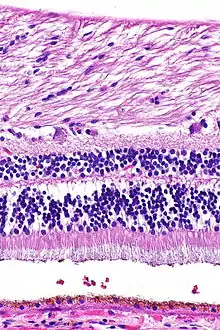

H&E stain

Hematoxylin and eosin stain (or haematoxylin and eosin stain or hematoxylin-eosin stain; often abbreviated as H&E stain or HE stain) is one of the principal tissue stains used in histology.[1][2][3] It is the most widely used stain in medical diagnosis[1] and is often the gold standard.[4] For example, when a pathologist looks at a biopsy of a suspected cancer, the histological section is likely to be stained with H&E.

H&E is the combination of two histological stains: hematoxylin and eosin. The hematoxylin stains cell nuclei a purplish blue, and eosin stains the extracellular matrix and cytoplasm pink, with other structures taking on different shades, hues, and combinations of these colors.[5][6] Hence a pathologist can easily differentiate between the nuclear and cytoplasmic parts of a cell, and additionally, the overall patterns of coloration from the stain show the general layout and distribution of cells and provides a general overview of a tissue sample's structure.[7] Thus, pattern recognition, both by expert humans themselves and by software that aids those experts (in digital pathology), provides histologic information.

Hematoxylin principally colors the nuclei of cells blue or dark-purple,[6][15][14] along with a few other tissues, such as keratohyalin granules and calcified material. Eosin stains the cytoplasm and some other structures including extracellular matrix such as collagen[5][7][14] in up to five shades of pink.[8] The eosinophilic (substances that are stained by eosin)[5] structures are generally composed of intracellular or extracellular proteins. The Lewy bodies and Mallory bodies are examples of eosinophilic structures. Most of the cytoplasm is eosinophilic and is rendered pink.[10][15] Red blood cells are stained intensely red.